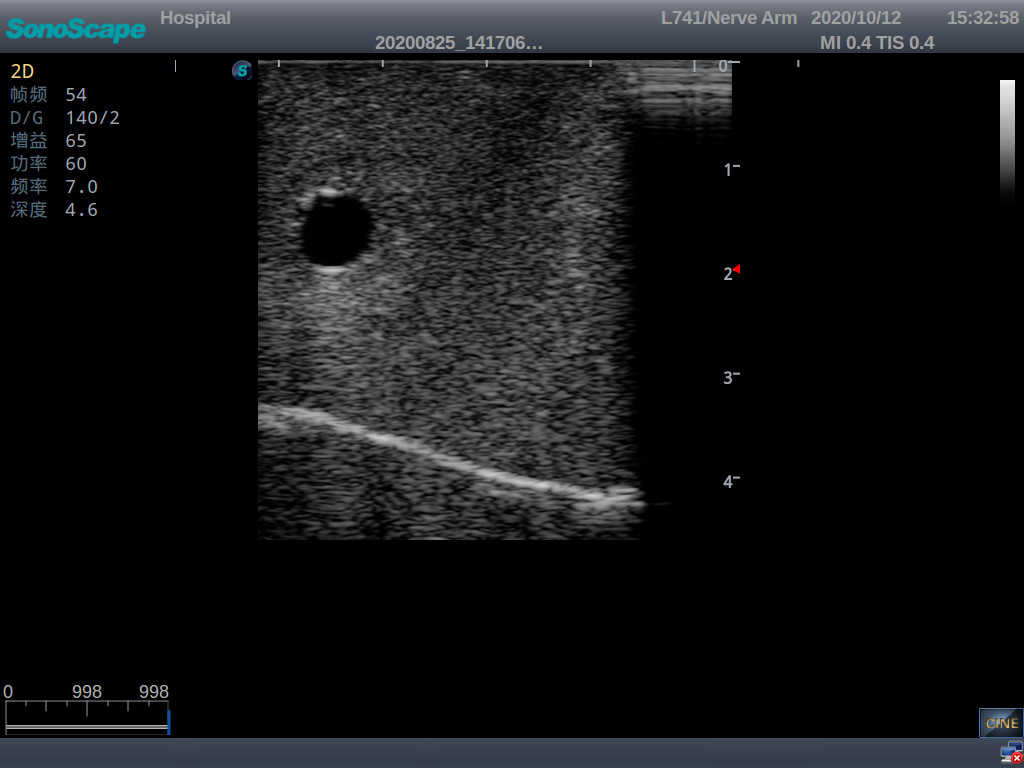

2)  The puncture module supports using a clinical real ultrasound machine to observe clear images such as right internal jugular vein, right common carotid artery, superior vena cava, right brachiocephalic vein, right brachiocephalic trunk, right subclavian vein, right subclavian artery, etc.

3)  The puncture pad at the arm is made of high-molecular ultrasound material, close to real skin. It can support the use of real ultrasound machines, and the images of tissue structures (skin, subcutaneous tissue, blood vessels) under ultrasound are clear and real

5)  The guide wire’s march can be observed under the guidance of ultrasound, and also whether the catheter is placed correctly can be detected